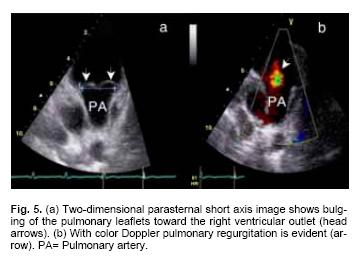

Mitral, tricuspid and aortic valve prolapse was diagnosed by previously established criteria.13,15 Echocardiographic evidence of mitral valve prolapse corresponded to a posterior mitral displacement of at least 2 mm during late systole or a 3 mm displacement throughout systole on M–mode tracings, which was confirmed by billowing of one or both mitral leaflets superior to the plane of the mitral annulus in two–dimensional parasternal long axis views. Pulmonary valve prolapse was defined as the bowing of one or more leaflets into the right ventricular outlet.

Dilatation of the pulmonary annulus was found in 47 patients (70%) with associated dilatation of the main pulmonary artery in nine (13.5%) (Figs, 1a, b).

Mitral valve prolapse was found in 21 patients (95.5%) of Group I and in 32 (72.7%) of Group II (p = ns, Figs. 2a, b). Tricuspid valve prolapse was detected in 18 (81.8%) patients of Group I and in 26 (59.1%) of those in Group II (p = ns, Fig. 3). Aortic valve prolapse was found in 5 patients (22.7%) of Group I and in 5 (11.4%) of Group II (p = ns, Figs. 4a, b). Furthermore, pulmonary valve prolapse was found in 10 patients (45.5%) of Group I and in 7 (15.9%) of Group II (p <0.03, Table IV, Figs. 5a, b). In contrast, mitral, tricuspid, aortic and pulmonary valve prolapse was not observed in both control groups (p < 0.001) (Fig. 6).

In two series of MFS patients, mitral valve prolapse has been found in up to 80% of cases. This percentage is in agreement with our findings of mitral valve prolapse in 80.3%.13,14 The mitral was the most commonly affected heart valve, followed by the tricuspid and pulmonary valves. In this cohorts there was a sizable percent of cases (21.2%) with pulmonary valve prolapse in association with pulmonary regurgitation, which was significantly more frequent in Group I (p = 0.006) when it was compared with control groups. Recent surgical and pathologic studies have demonstrated myxomatous degeneration of aortic, tricuspid and mitral valves. At present, prognostic implications of isolated pulmonary valve prolapse or in association with pulmonary valve regurgitation have not been explored in Marfan syndrome. Since the pulmonary valve is made up of essentially the same tissue as the aortic valve, it would be reasonable to assume that both valves could be equally affected in patients with Marfan syndrome. Moreover, it has been suggested that the abnormalities are not confined to a single valve but may involve all of the endocardial tissue, leading to multivalvular compromise. Indeed, in our series 63% of patients had involvement of two or more heart valves.